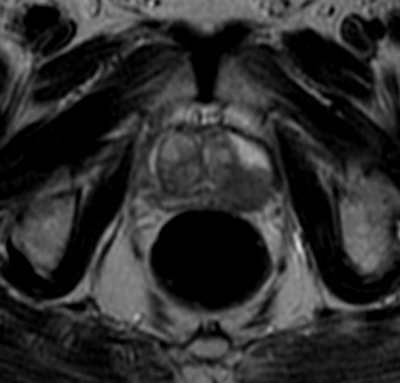

A normally fit and well 62-year-old gentleman with a PSA of 6ng/ml has this axial T2-weighted MRI. His prostate biopsies demonstrated Gleason 3+3 disease from the left lobe and digital rectal examination (DRE) revealed a firm left lobe.

- What does the MRI show?

There is a T2b-hypointense nodule in the left lobe of the prostate on MRI. It appears to be organ-confined.